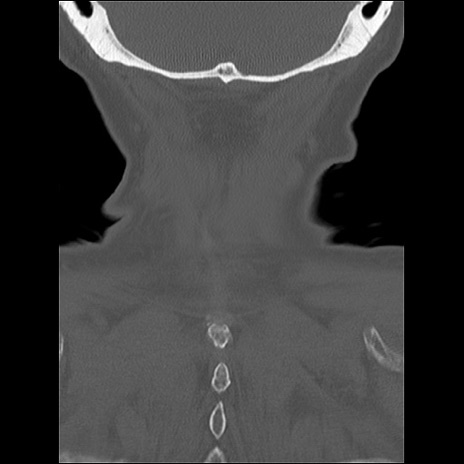

症例48 頚椎CT(冠状断像)

頚椎CT